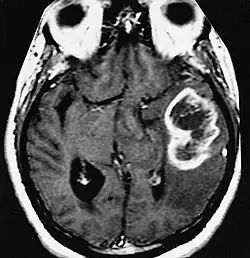

| An example of a ring-enhancement around a lesion in gliobastoma. In tumefactive multiple sclerosis, the ring-enhancement is open, not forming a complete ring. |

Diagnosis of tumefactive MS is commonly carried out using magnetic resonance imaging (MRI) and proton MR spectroscopy (H-MRS). Diagnosis is difficult as tumefactive MS may mimic the clinical and MRI characteristics of a glioma or a cerebral abscess. However, as compared to tumors and abscesses, tumefactive lesions have an open-ring enhancement as opposed to a complete ring enhancement.[1] Even with this information, multiple imaging technologies have to be used together with biochemical tests for accurate diagnosis of tumefactive MS.[36]

MRI diagnosis is based on lesions that are disseminated in time and space, meaning that there are multiple episodes and consisting of more than one area.[39] There are two kinds of MRI used in the diagnosis of tumefactive MS, T1-weighted imaging and T2-weighted imaging. Using T1-weighted imaging, the lesions are displayed with low signal intensity, meaning that the lesions appear darker than the rest of the brain. Using T2-weighted imaging, the lesions appear with high signal intensity, meaning that the lesions appear white and brighter than the rest of the brain. When T1-weighted imaging is contrast-enhanced through the addition of gadolinium, the open ring enhancement can be viewed as a white ring around the lesion.[40] A more specific MRI, Fluid attenuation inversion recovery (FLAIR) MRI show the signal intensity of the brain. Subjects with tumefactive multiple sclerosis may see a reduction of diffusion of the white matter in the affected area of the brain.[11]